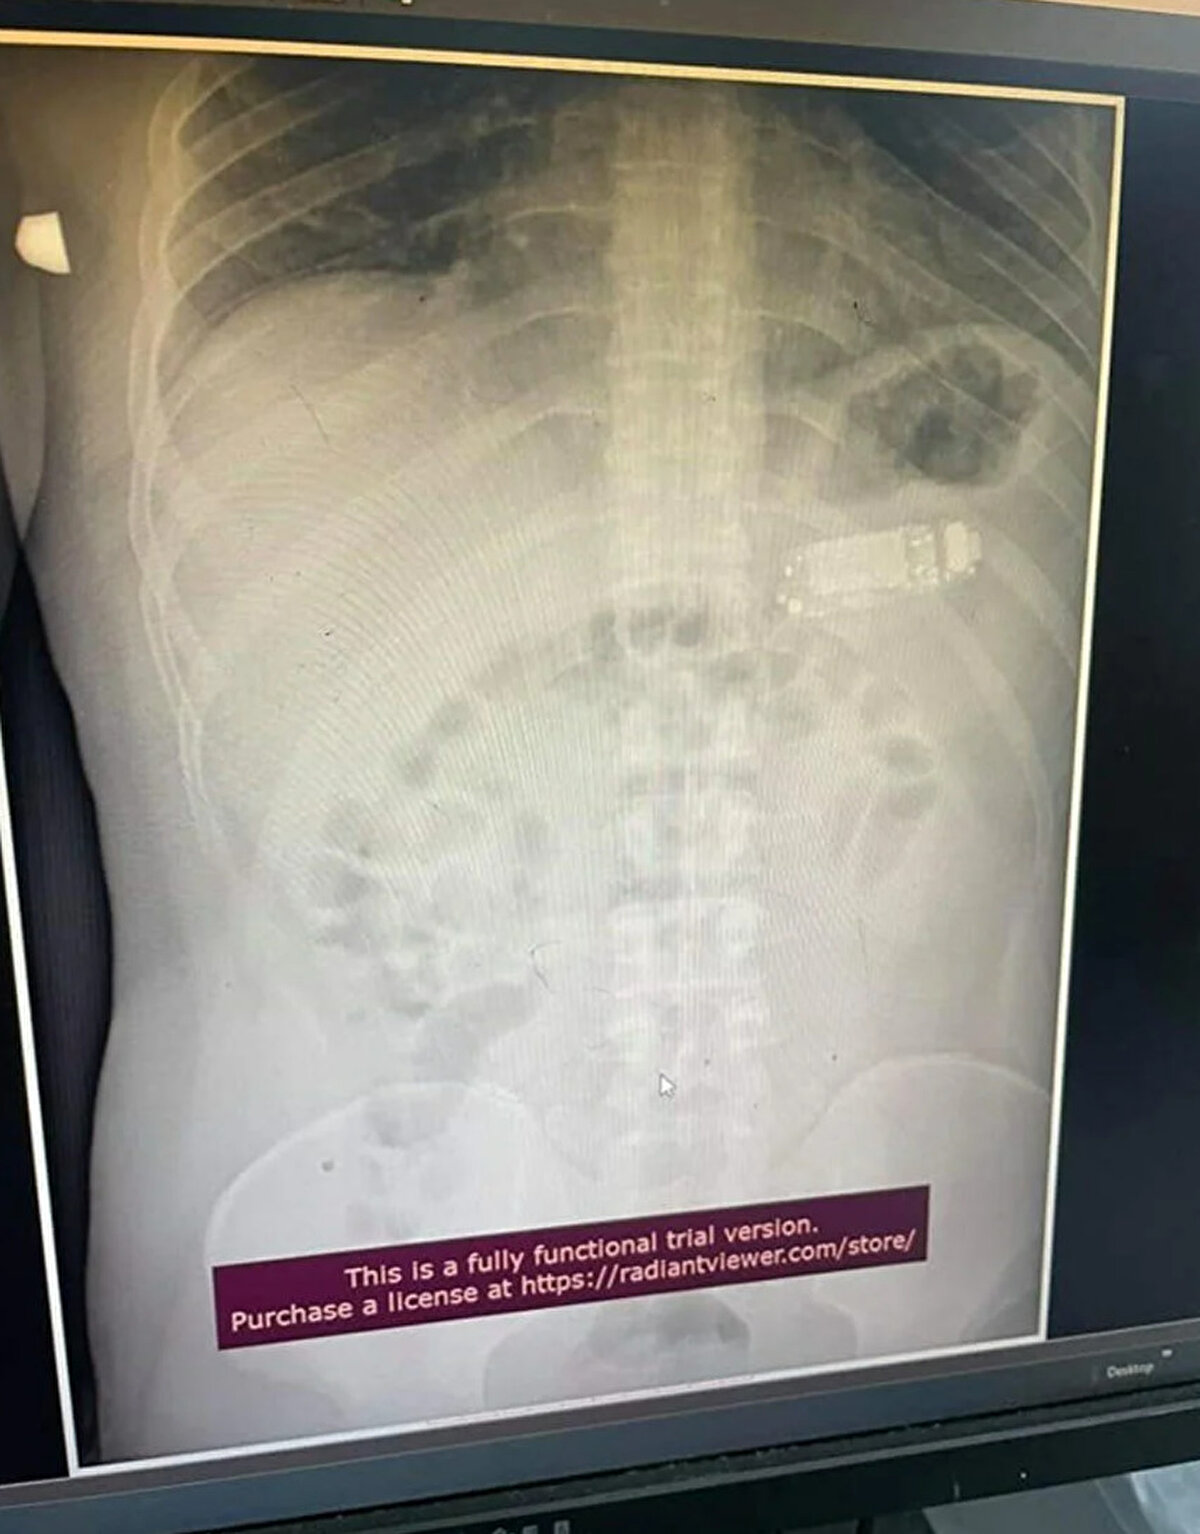

Güneydoğu Avrupa'da denize kıyısı olmayan bir ülke olan Kosova'nın başkenti Priştine'de doktorlar, Nokia 3310 model bir cep telefonunu yutan adamı ameliyat etti. Telefonun adı açıklamayan adamın midesinde dört gün kaldığı belirtildi. Başarılı operasyonu gerçekleştiren sağlık ekibinin başındaki doktor Skender Teljaku, adamın midesinden çıkarılan telefonun fotoğrafları ile röntgen ve endoskop görüntülerini Facebook'ta yayınladı.

Teljaku yaptığı açıklamada, tıbbi ekibin telefonu mideyi kesmeden, endoskop olarak bilinen özel cihazlar kullanarak üç ayrı parçaya ayırmayı başardığını söyledi. Teljaku, ayrıca yaklaşık iki saat süren işlem sırasında "herhangi bir komplikasyon" yaşanmadığını sözlerine ekledi. Bununla birlikte 33 yaşındaki adamın telefonu yuttuktan sonra yaşadığı acı nedeniyle Kosova'nın başkentindeki hastaneye gitmeye karar verdiği aktarıldı. Teljaku, özellikle bataryanın en tehlikeli parçası olduğunu, patlayarak hayatı potansiyel olarak tehlikede olan adamın bağırsaklarına kimyasal salabileceğini söyledi.